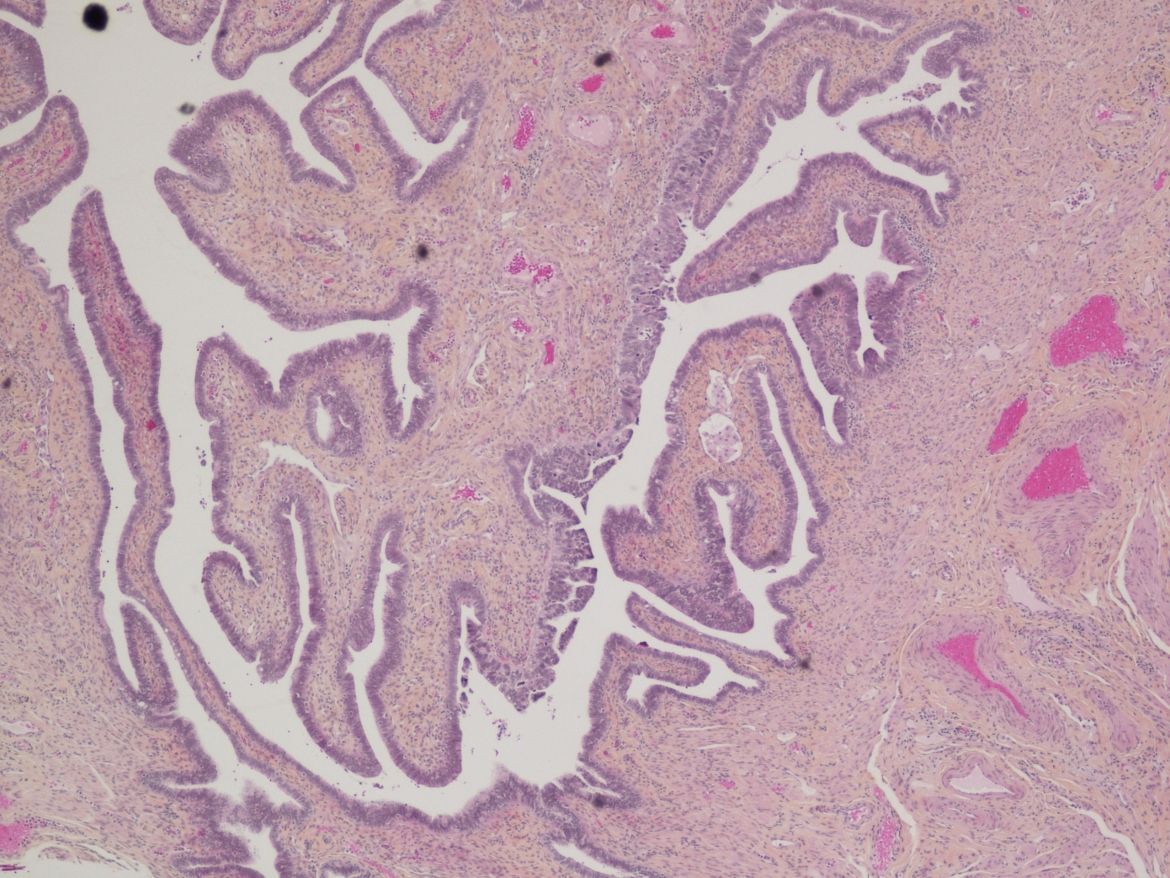

An image of cancerous tissue as seen through a microscope in the histology lab